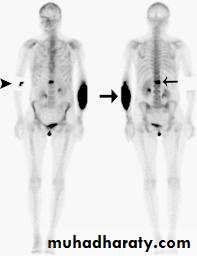

Radioscintigraphy

Bone scans with 99mTc-MDP are themost sensitive method of detecting ‘silent’ metastatic

deposits in bone; areas of increased activity are selected for x-ray examination.